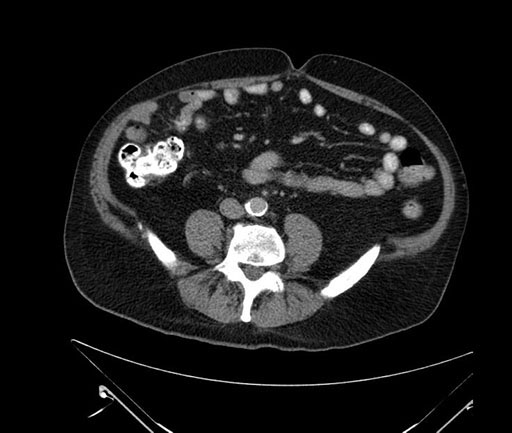

Whipple (pancreaticoduodenectomy) [case 7]

Axial - stented

Imaging analysis

Based on your CT findings, which issue(s) would give reason for "planned slowing down moment(s)" in this case?

Considering a standard Whipple procedure, what step(s) of the operation would you do differently in this case?